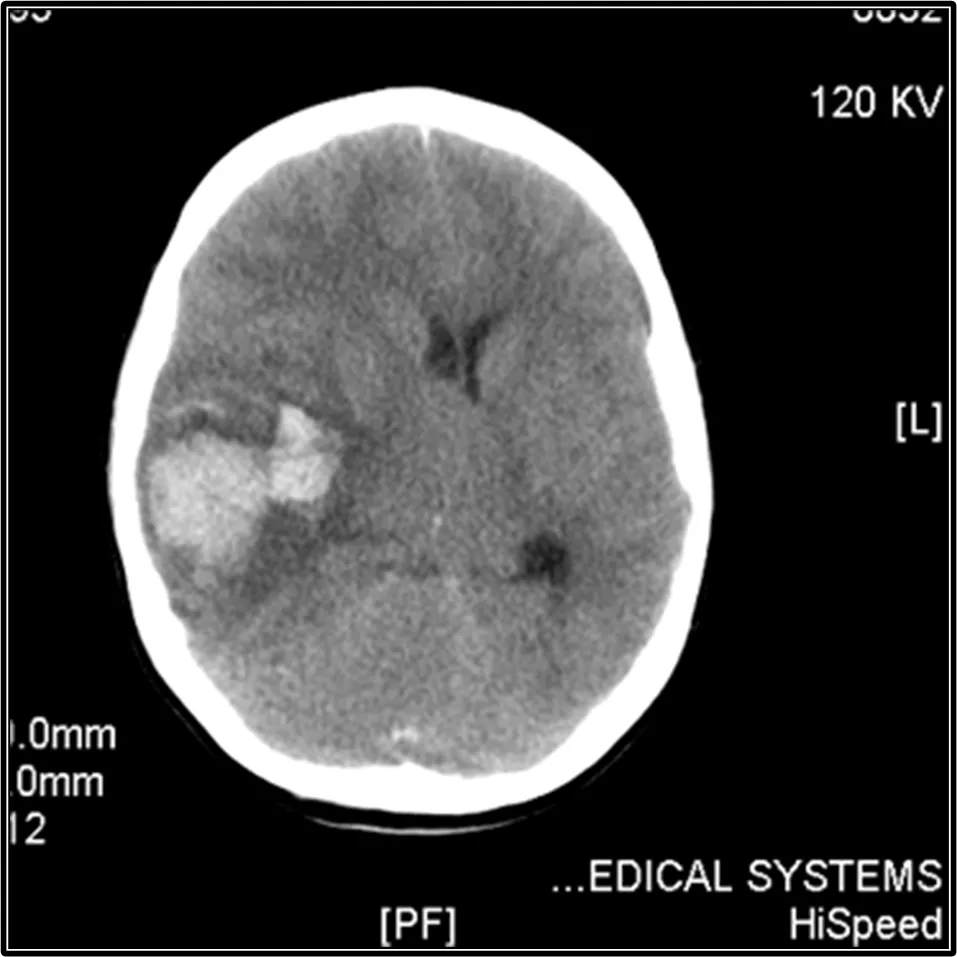

Внутричерепные кровоизлияния

• Lilleyman 1994 — 14 случаев за 20 лет (0,1%)

• ICIS Kuhne 2003 0,002%

Тяжелые кровотечения 3-5%

• ЖКК, урогенитальные кровотечения, носовые кровотечения, меноррагии